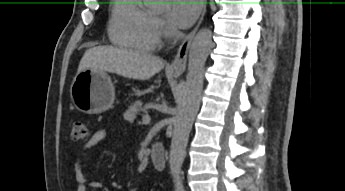

Современным высокоинформативным способом выявления патологических изменений поджелудочной железы является мультиспиральная компьютерная томография с прицельным сканированием органа.

При помощи специальных цифровых приложений данные, полученные при сканировании, преобразуются в трехмерные изображения органа, что дополнительно повышает точность и достоверность диагностики заболеваний поджелудочной железы.

Контрастирование позволяет отличить зоны воспаления, деструкции, разрастания фиброзной ткани и опухолевой трансформации от сохраненной паренхимы поджелудочной железы. КТ поджелудочной железы с контрастированием дает исчерпывающую информацию о состоянии органа и патологических процессах в нем.

Что покажет КТ поджелудочной железы

- злокачественные и доброкачественные опухоли, включая инсулиному, глюкагоному, випому, гастриному, рак поджелудочной железы;

- кальцинаты в панкреатических протоках;

- острую и хроническую формы панкреатита;

- кисты и псевдокисты поджелудочной железы